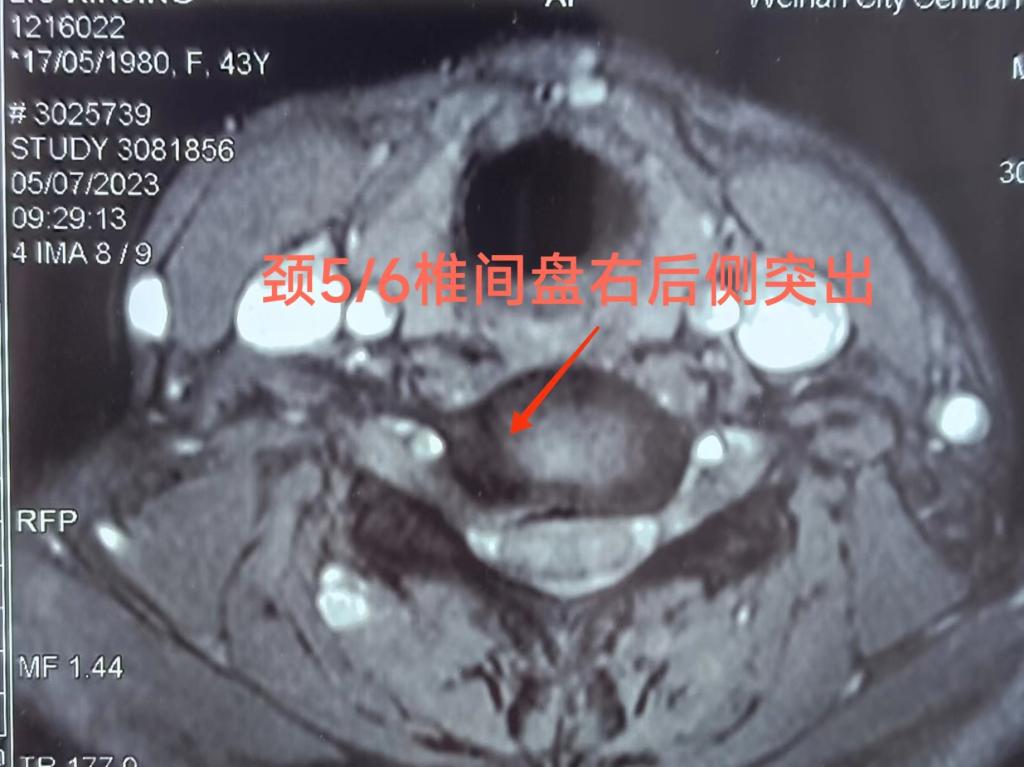

患者女性,43岁,入院时右上肢抽痛、麻木1周,行颈椎MR提示:颈4/5、5/6椎间盘突出,颈2.3后纵韧带骨化,颈椎曲度反弓。患者右肩部、右上肢抽痛明显,不能平卧,夜不能寐,痛苦万分。

入院后骨一科主任程福宏,副主任医师葛大明经查体,阅读影像学资料,确定病灶为颈5/6椎间盘。科室讨论认为:传统开放手术,需要多节段颈椎间融合内固定,手术创伤较大,术后恢复时间长,颈椎活动度后期有一定影响。考虑患者年轻,依照快速康复(ERAS)理念,准备微创在椎间孔镜下行后路颈5/6椎间盘摘除术。

经过充分术前沟通、准备,7月11日早晨进行手术,历时1个半小时,顺利结束。术中见颈5/6椎间盘右后侧突出,髓核游离,压迫颈6右侧神经根,取出髓核后,神经根完全松解。